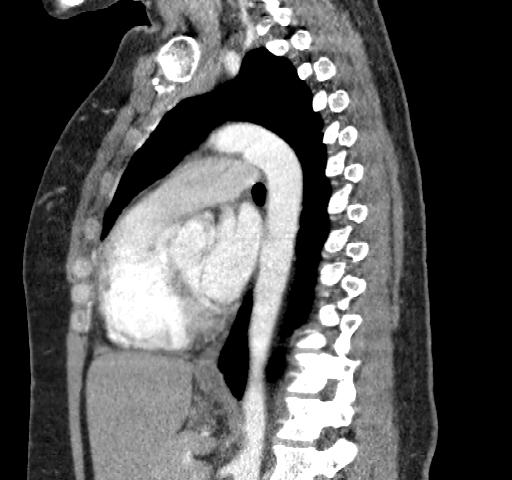

40 year old female. Breast implants 17 years ago, most likely Dow Corning. Symptoms from upper body for 6-7 years. Pain in breasts, ribs, back, neck. Skin rash. Headache and dizziness, weakness, numbness and vision disturbing. Sudden sleep episodes. Painful lymph-notes. These images are from 2010 and diagnose results were "No findings". Patient is scheduled for explantation in mid Feb. 2012